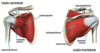

Síndrome do impacto?

- Tendinite do supraespinhoso (manguito rotador)

- Compressão do tendão entre o acrômio e úmero

Síndrome do Impacto. Fatores de risco? (4)